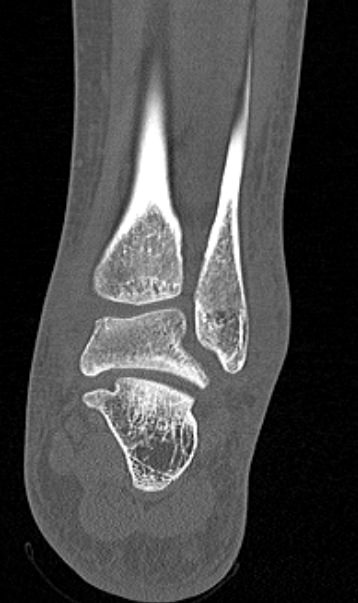

Во время исследования рентгеновская трубка томографа вращается вокруг исследуемой области и производит множество послойных снимков с шагом от 0,5 мм. Полученные снимки поперечного сечения с помощью компьютерной программы могут быть преобразованы в 3D-изображения исследуемого органа. Это позволяет выявлять различные патологические процессы на начальных стадиях и назначать своевременное лечение.

За счет быстроты, доступности и неинвазивности (то есть исследование не требует вмешательства в организм) метод КТ особенно востребован в ортопедии и травматологии. Мультиспиральная КТ лучше всего визуализирует плотные ткани, такие как кости и хрящи. Поэтому, в первую очередь, применяется для диагностики травм суставов (вывихов, подвывихов, переломов).

В отличие от обычного рентгена, при котором изображения костных структур накладываются друг на друга, что затрудняет диагностику, компьютерная томография дает возможность увидеть объемную модель сустава, наглядно оценить пространственное соотношение внутрисуставных структур, суставных поверхностей, расположение костных отломков при переломах и травмах. Это особенно важно в ходе подготовки к оперативному вмешательству и в послеоперационном периоде для оценки успешности проведенной операции.